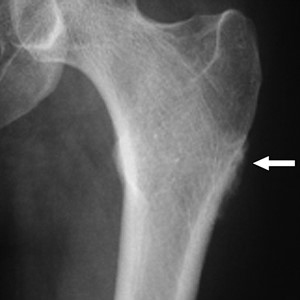

На рентгене эта опухоль похожа на вдавливание в форме блюдца и склерозированным краем в пораженной кости. Иногда также отмечают частично разрушенную кортикальную пластинку. В этом случае границы опухоли с окружающей костью становится неопределенной и расплывчатой. В месте, где опухоль соприкасается с непораженной частью кости в большинстве случаев видна треугольная склеротическая шпора.